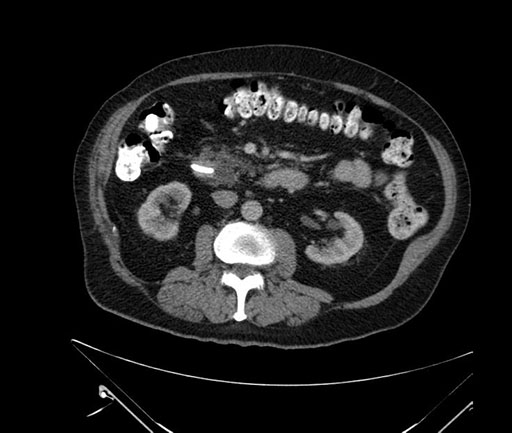

Axial - stented